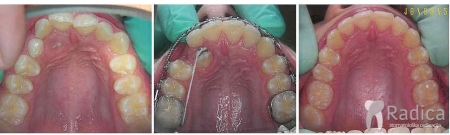

Duboki zagriz, hypodontia (nedostatak) gornjeg desnog lateralnog sjekutića i impakcija gornjeg lijevog očnjaka u nepcu:

Uslijed resorpcije korijena desnog lateralnog sjekutića koji je morao biti izvađen ortodontskom terapijom smo dobili prostor za daljnju protetsku nadoknadu zuba.